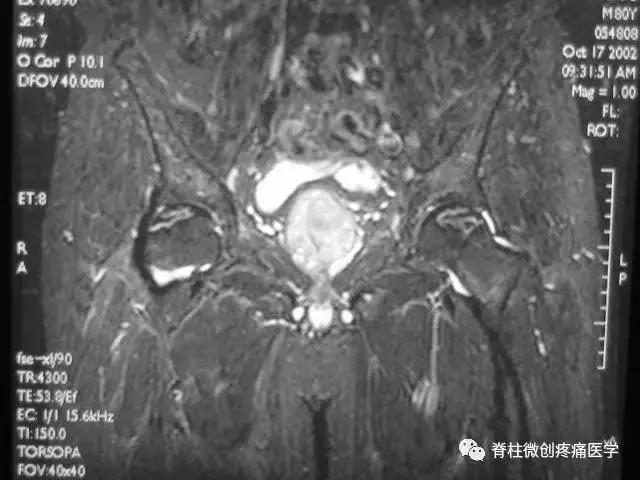

■ Ⅲ期

髋关节间隙正常,无狭窄。

股骨头表面毛糙、开始变形。

软骨下皮质出现骨折,进一步发展出现轻微塌陷、阶梯状改变。

新月体形成:新月体代表无法修复的坏死骨发生引力性骨折,在T1W上为带状低信号区,T2W上,由于细胞内液渗出或关节液充填骨折线而呈高信号

股骨头表面软骨的完整性受到一定影响。